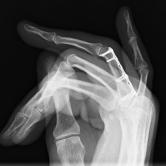

Röntgenbilder